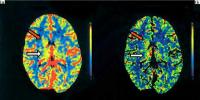

Abbildung 1: Die postiktale Perfusions-CT zeigte ein gesteigertes zerebrales Blutvolumen (a) und einen gesteigerten zerebralen Blutfluß (b) im rechten Caput nuclei caudati (oranger Pfeil) und im Nucleus lentiformis sowie in einem geringeren Ausmaß im Bereich des rechten Thalamus (weißer Pfeil).